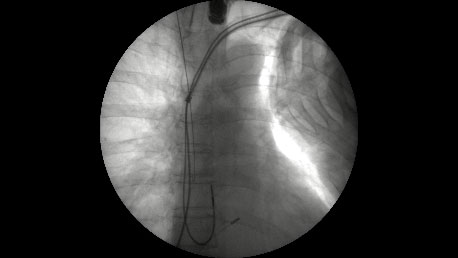

当院が施設認定を受け、「経静脈電極抜去術(レーザーシースを用いるもの)によるリード抜去」の第一例目を2016年6月9日に開始して1年以上経過しました。これまで他県に依頼してきた手技が、鹿児島でもようやく可能となり、南九州では初めてのことでした。第一例目開始から2017年6月2日までの初期の1年間で、15症例、計28本のリード抜去術を施行し、現在まで全例のリード抜去に成功しています。

リード抜去は心タンポナーデ、鎖骨下と上大静脈の血管損傷や血気胸などの重篤な合併症があり、すぐに開胸して止血術を行わなければならないために心臓血管外科の待機下で施行が必要です。